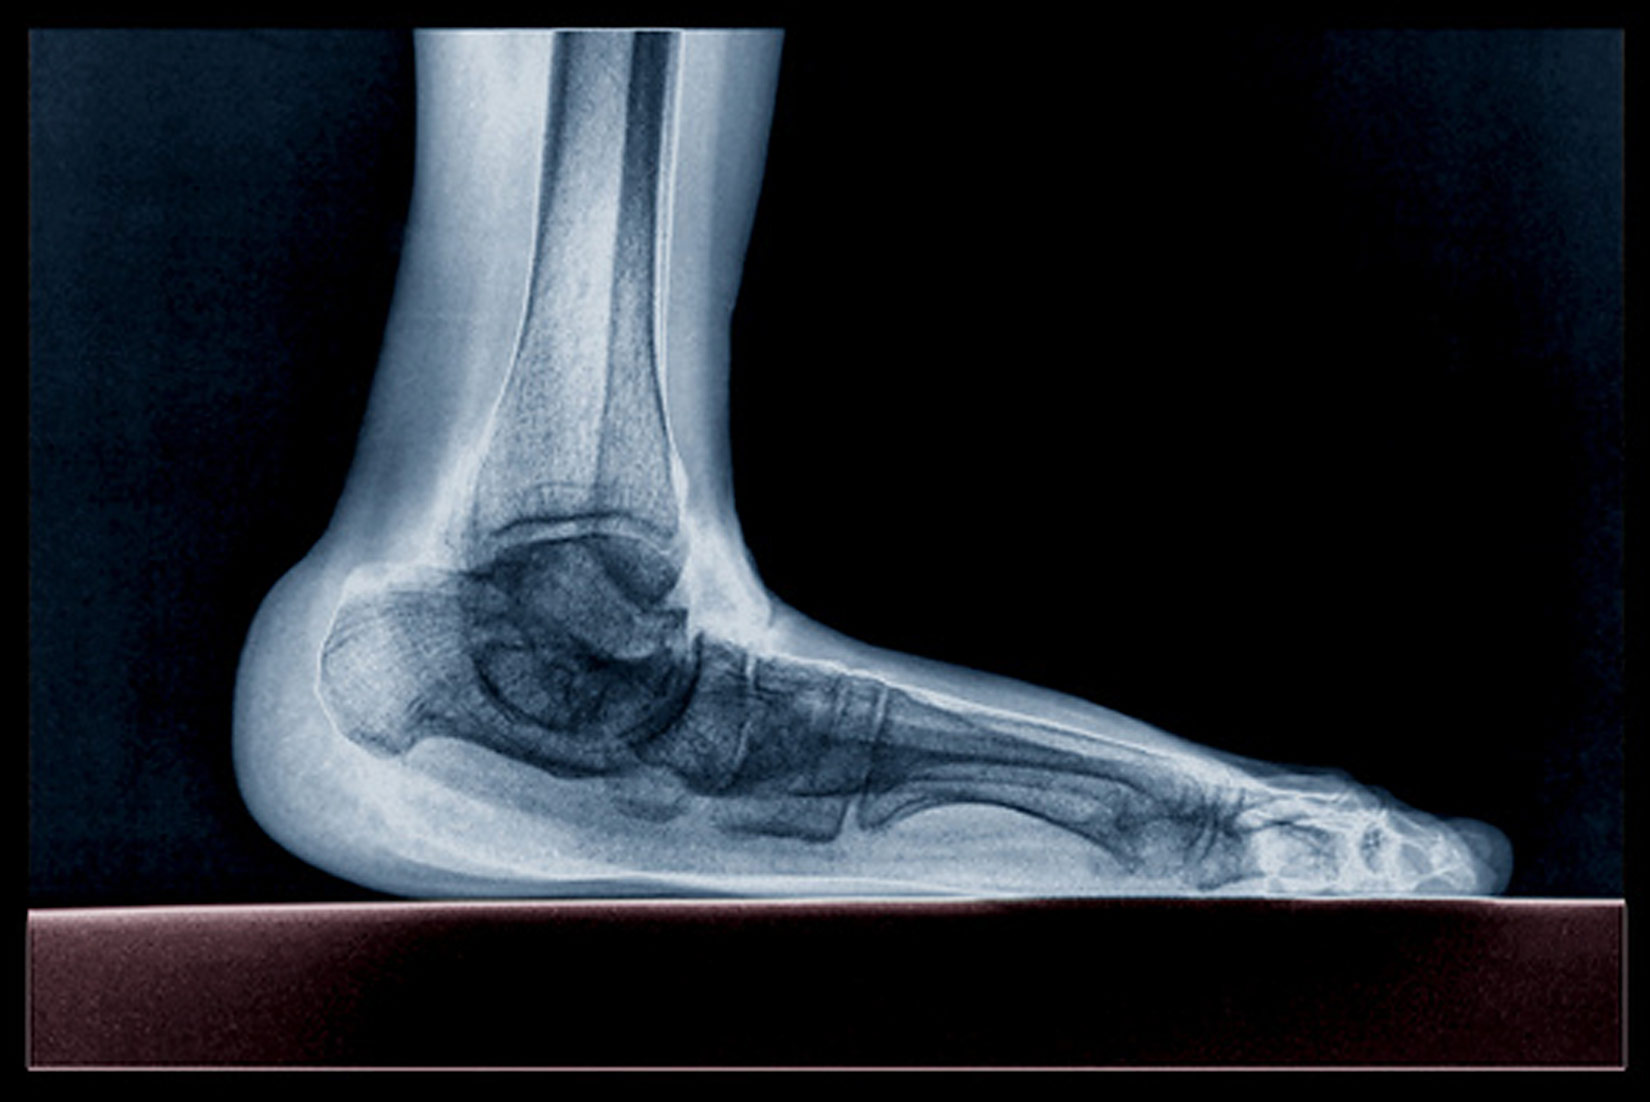

Najveća koncentracija kosti nalazi se u području šaka i stopala.

Ti su dijelovi kostura među najpokretljivijima.

Stopala nose težinu cijeloga tijela.

- Proučite prikaz raspodjele težine na kosti stopala.

- Koja je bitna razlika između normalnoga i spuštenoga stopala?

Osobe koje imaju spušteno stopalo, trebaju vježbati mišiće u području stopala.

Neke od vježbi koje se preporučuju jest bosonogo hodanje po neravnome terenu, npr. šljunku ili plaži.